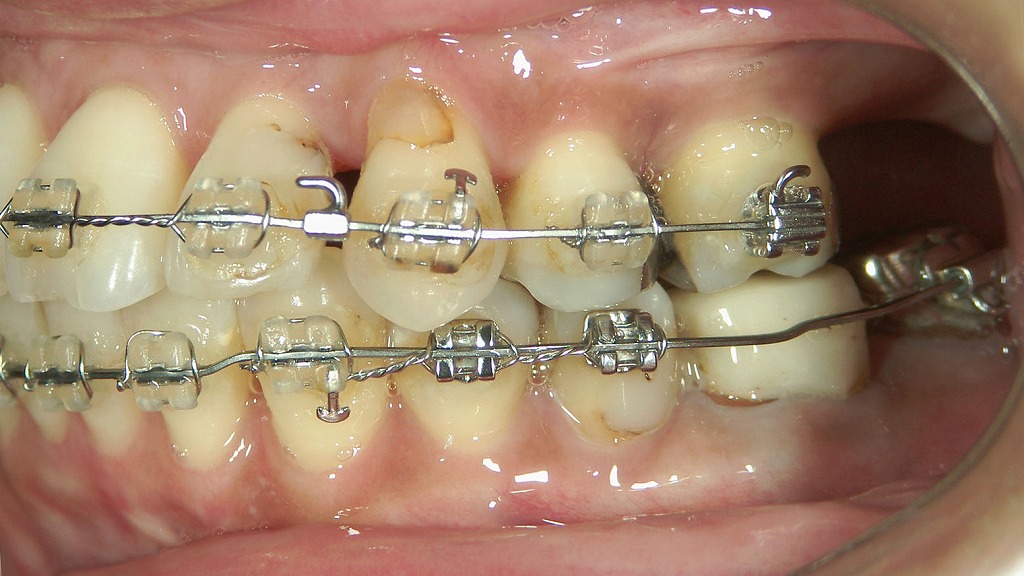

- 4.2. 🦠 八重歯周辺にできた虫歯の症例

- 4.2.1. 🦷 各部位の説明

- 4.2.1.1. ① 上顎右側側切歯(2番)

- 4.2.1.2. ② 上顎右側犬歯(3番)

- 4.2.1.3. 🪥 総評・対応の目安

左上顎の犬歯が八重歯

向かって右側上顎の犬歯が八重歯になっています。八重歯とは正常な歯列から犬歯がはみ出した状態を指していいます。

この症例では向かって左側の側切歯も歯列からはみ出しています。この様に凸凹した歯並びを乱杭歯とも呼んでいます。

同症例の咬合面観

向かって右側の犬歯と左側の側切歯が完全に歯列からはみ出しているのがわかります。

側切歯には歯の間に虫歯が認められます。

このようにガタガタの歯並びでは歯磨きがうまく出来ないため、虫歯が発生しやすくなります。

- プラーク(歯垢)がたまりやすい

- 八重歯の裏側に磨き残しができやすい

- 歯ぐきが腫れやすく、出血・炎症が慢性化しやすい

この結果、虫歯や歯周病が発症・悪化しやすくなるのです。特に八重歯の下部は汚れが溜まりやすいため、初期むし歯や歯周炎を見逃しがちです。

🦠 八重歯周辺にできた虫歯の症例

🦷 各部位の説明

① 上顎右側側切歯(2番)

赤い矢印の先端部、遠心側(右側の隣接面)に黒っぽい変色が確認できます。

→ **C2(エナメル質を越えて象牙質に達する虫歯)**の可能性が高く、進行性のう蝕が疑われます。穴はまだ浅いものの、早期治療が望ましい状態です。

② 上顎右側犬歯(3番)

この歯は**八重歯(叢生)の状態で、歯列よりやや外側に位置しています。

近心(2番との隣接面)に影や変色が見られ、虫歯の初期段階(C1〜C2)**の可能性があります。位置的に歯ブラシやフロスが届きにくいため、汚れが残りやすく虫歯が発生しやすい環境です。

🪥 総評・対応の目安

- 2番遠心部:早期に治療(コンポジットレジン修復など)を検討。

- 3番近心部:虫歯リスクが高いため、隣接面清掃を強化(デンタルフロス・歯間ブラシなど)。

- 叢生(八重歯)により清掃性が悪化しているため、定期的なプロフェッショナルケア(PMTC、エアフロー等)も有効です。